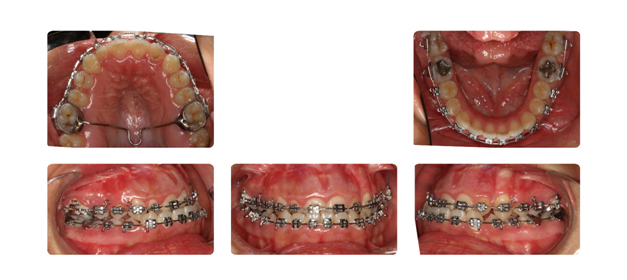

| بعد از قرارگیری دندانها در جای خود ومرتب شدن آنها فک نیز آماده جراحی میباشد: |

![]() |

| پس از جراحی فک وپایان درمان ارتدونسی دندانها و فک به نتیجه مطلوبی رسیده اند: |